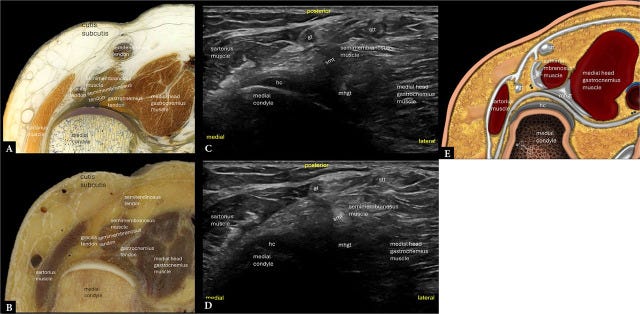

En la zona medial, la exploración se convierte en una especie de descenso por capas, como si estuviéramos desactivando un artefacto con múltiples niveles de protección. Primero, la sonda se orienta para identificar las estructuras más superficiales, y a partir de ahí, se profundiza con precisión quirúrgica. El primer hallazgo es el músculo sartorio, elegante y siempre en su sitio. Justo por detrás, aparece el tendón del grácil, que mantiene una posición estable y confiable, como Alfred para Batman: siempre detrás del protagonista, pero absolutamente necesario.

Siguiendo el recorrido, se encuentra el tendón del semitendinoso, que descansa justo encima del semimembranoso, este último ocupando una posición más profunda y robusta. En lo más profundo, como si custodiara la puerta trasera de la articulación, aparece la cabeza medial del gastrocnemio. Todo este conjunto se convierte en una sinfonía anatómica perfectamente orquestada.

En el extremo posteromedial de la tibia, el semimembranoso realiza su inserción. Este punto es una especie de ancla estructural que influye notablemente en la biomecánica de la región. Y justo cuando uno cree haberlo visto todo, Tamborrini sugiere mirar más allá: una evaluación dinámica de la unión menisco-capsular del cuerno posterior del menisco medial. El paciente debe colocarse en prono y realizar una flexión activa de rodilla contra resistencia. No se trata solo de ver estructuras, sino de entender cómo se comportan bajo presión. Como diría el maestro Yoda: “Revelador, el movimiento es”.

Y aún no se acaba. Con movimientos dinámicos de flexión y extensión de rodilla, también en prono, se pueden identificar fricciones entre estructuras tendinosas. Este tipo de observación permite detectar conflictos sutiles que, en estático, pasarían completamente desapercibidos. Justo por debajo, en el plano profundo, aparecen estructuras igual de importantes: el cuerno posterior del menisco medial, el cóndilo femoral medial y el cartílago hialino que recubre la meseta tibial, brillante y anecoico, como si hubiera sido pulido por Tony Stark.